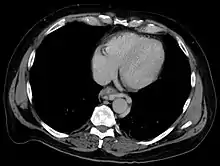

Esophageal varices are extremely dilated sub-mucosal veins in the lower third of the esophagus.[1] They are most often a consequence of portal hypertension,[2] commonly due to cirrhosis.[3] People with esophageal varices have a strong tendency to develop severe bleeding which left untreated can be fatal. Esophageal varices are typically diagnosed through an esophagogastroduodenoscopy.[4]

The upper two thirds of the esophagus are drained via the esophageal veins, which carry deoxygenated blood from the esophagus to the azygos vein, which in turn drains directly into the superior vena cava. These veins have no part in the development of esophageal varices. The lower one third of the esophagus is drained into the superficial veins lining the esophageal mucosa, which drain into the left gastric vein, which in turn drains directly into the portal vein. These superficial veins (normally only approximately 1 mm in diameter) become distended up to 1–2 cm in diameter in association with portal hypertension.

Normal portal pressure is approximately 9 mmHg compared to an inferior vena cava pressure of 2–6 mmHg. This creates a normal pressure gradient of 3–7 mmHg. If the portal pressure rises above 12 mmHg, this gradient rises to 7–10 mmHg.[5] A gradient greater than 5 mmHg is considered portal hypertension. At gradients greater than 10 mmHg, blood flowing through the hepatic portal system is redirected from the liver into areas with lower venous pressures. This means that collateral circulation develops in the lower esophagus, abdominal wall, stomach, and rectum. The small blood vessels in these areas become distended, becoming more thin-walled, and appear as varicosities.

Dilated submucosal veins are the most prominent histologic feature of esophageal varices. The expansion of the submucosa leads to elevation of the mucosa above the surrounding tissue, which is apparent during endoscopy and is a key diagnostic feature. Evidence of recent variceal hemorrhage includes necrosis and ulceration of the mucosa. Evidence of past variceal hemorrhage includes inflammation and venous thrombosis.